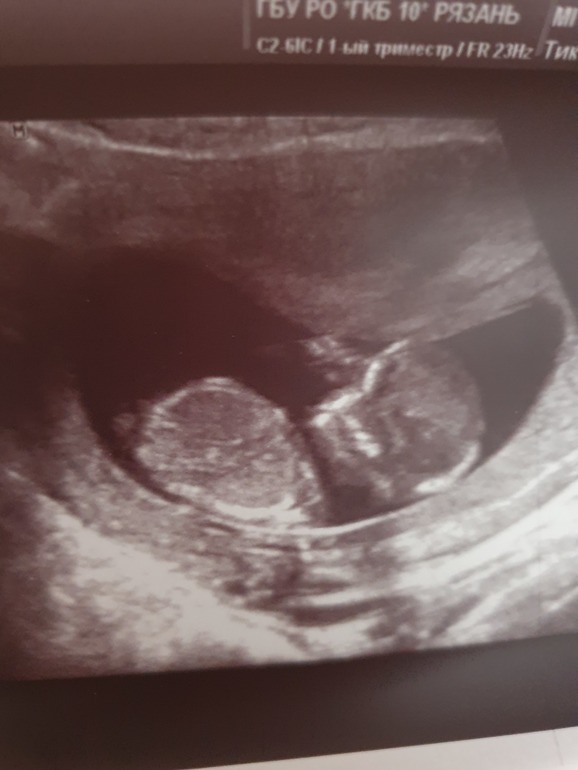

Вот и прошел 1 скрининг 😊

У нас все хорошо, уже 54мм!😊 Интересно кто тут у нас прячется , по фото мне кажется девочка))) Врач все делала молчком, по описанию все отлично)